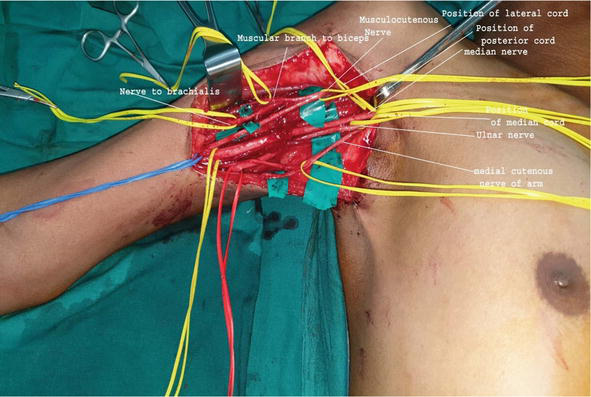

Plexus surgery is a specialized surgical treatment used to repair or reconstruct damaged nerve networks known as plexuses. These nerve networks control important functions such as movement, sensation, and muscle coordination in different parts of the body.

Plexus surgery involves advanced microsurgical techniques such as nerve repair, nerve grafting, and nerve transfer to restore nerve function. Early treatment and expert surgical care can significantly improve recovery and help patients regain strength and mobility.